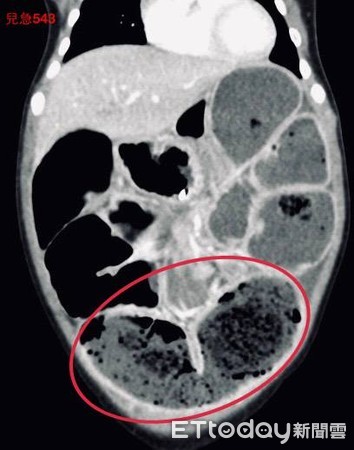

▲電腦斷層發現腸道塞滿大便。(圖/吳昌騰醫師提供)

小孩排便量減少要注意!一名女童連續2週解便不乾淨,近日更連續3天出現食慾變差、嘔吐症狀,被診所轉往急診治療。醫師觸診發現腹部有點脹,經超音波與電腦斷層掃描,發現小腸、大腸卡滿大便,且已經造成腸阻塞,由於藥物治療未見改善,只能透過腹腔鏡手術將宿便取出。